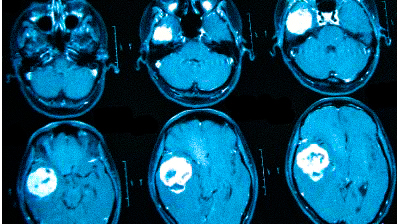

МР-томография позволяет выявить опухоли головного мозга, нарушения кровообращения, сосудистые поражения (например, аневризмы) и последствия различных заболеваний, включая инсульт. Это обследование помогает определить наличие серьезных заболеваний, которые могут проявляться хроническими или периодическими головными болями.

МРТ головного мозга может выявить:

- опухолевые процессы (доброкачественные и злокачественные);

- последствия травм (гематомы, кровоизлияния);

Онкологи подчеркивают, что при нарастающих головных болях, сопровождающихся необъяснимыми симптомами (обмороками, ухудшением памяти, выпадением полей зрения, давлением на глазные яблоки и др.), необходимо в первую очередь исключить опухолевую патологию.

Частые головные боли могут иметь различные причины, и иногда они сигнализируют о серьезном заболевании. В 90% случаев после определения причины возможно адекватное лечение, которое улучшит качество жизни. Состояния, для которых характерна цефалгия, включают: